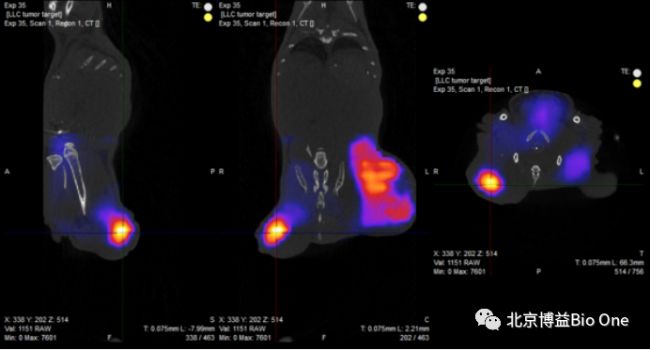

3D 近紅外(NIR)斷層掃描光學成像系統是一種創新的設備,可在單個平臺上提供具有高質量解剖學參考的3D NIR光學圖像。基于熒光發射斷層掃描(FLECT)技術的InSyTe平臺為臨床前小型動物模型的全身成像和活體表征提供了無與倫比的功能。通過采用同軸一體化的設計,將FLECT和X射線CT這兩種3D成像單元集成到同一臺設備中;利用已獲專利認證的旋轉式機架設計,來收集得到實驗動物周身360°范圍內的光學與X射線投影;NIR探針與激光激發結合使用,可進一步提高3D數據采集的靈敏度(達到pM級別)和精確度,尤其適用于利用熒光成像手段檢測低劑量和深層組織信號的實驗;強大的圖像重建算法利用分段的X射線CT數據,評估動物體內光學特性的變化,并提供準確的重建可視化效果。

Figure2. 注射NIR探針后的小鼠掃描圖像